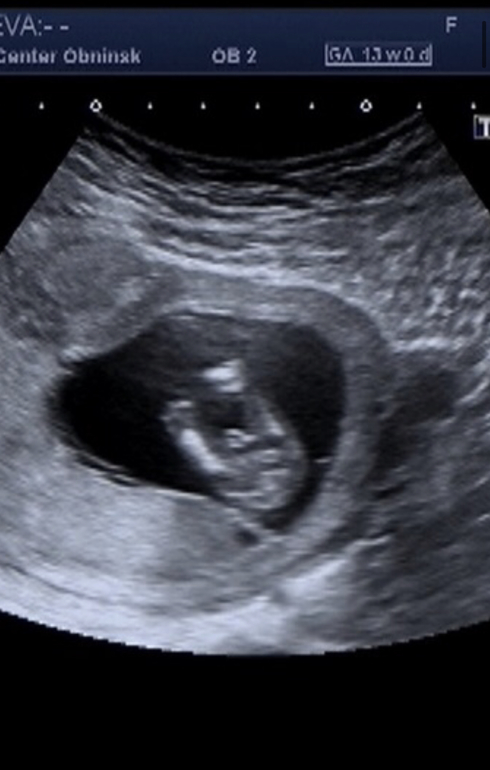

Первая беременность (мальчик)

УЗИ, КТГ, доплерДве недели назад была на узи, тогда ребёнок ещё не дорос до скрининга, сказали придти через 2 недели (тогда было 11 недель), предположительно но не точно, сказали похоже на девочку. Мы с мужем обрадовались, т.к. первый у нас сынок. Думали сестренка будет. Рано радовались 😂